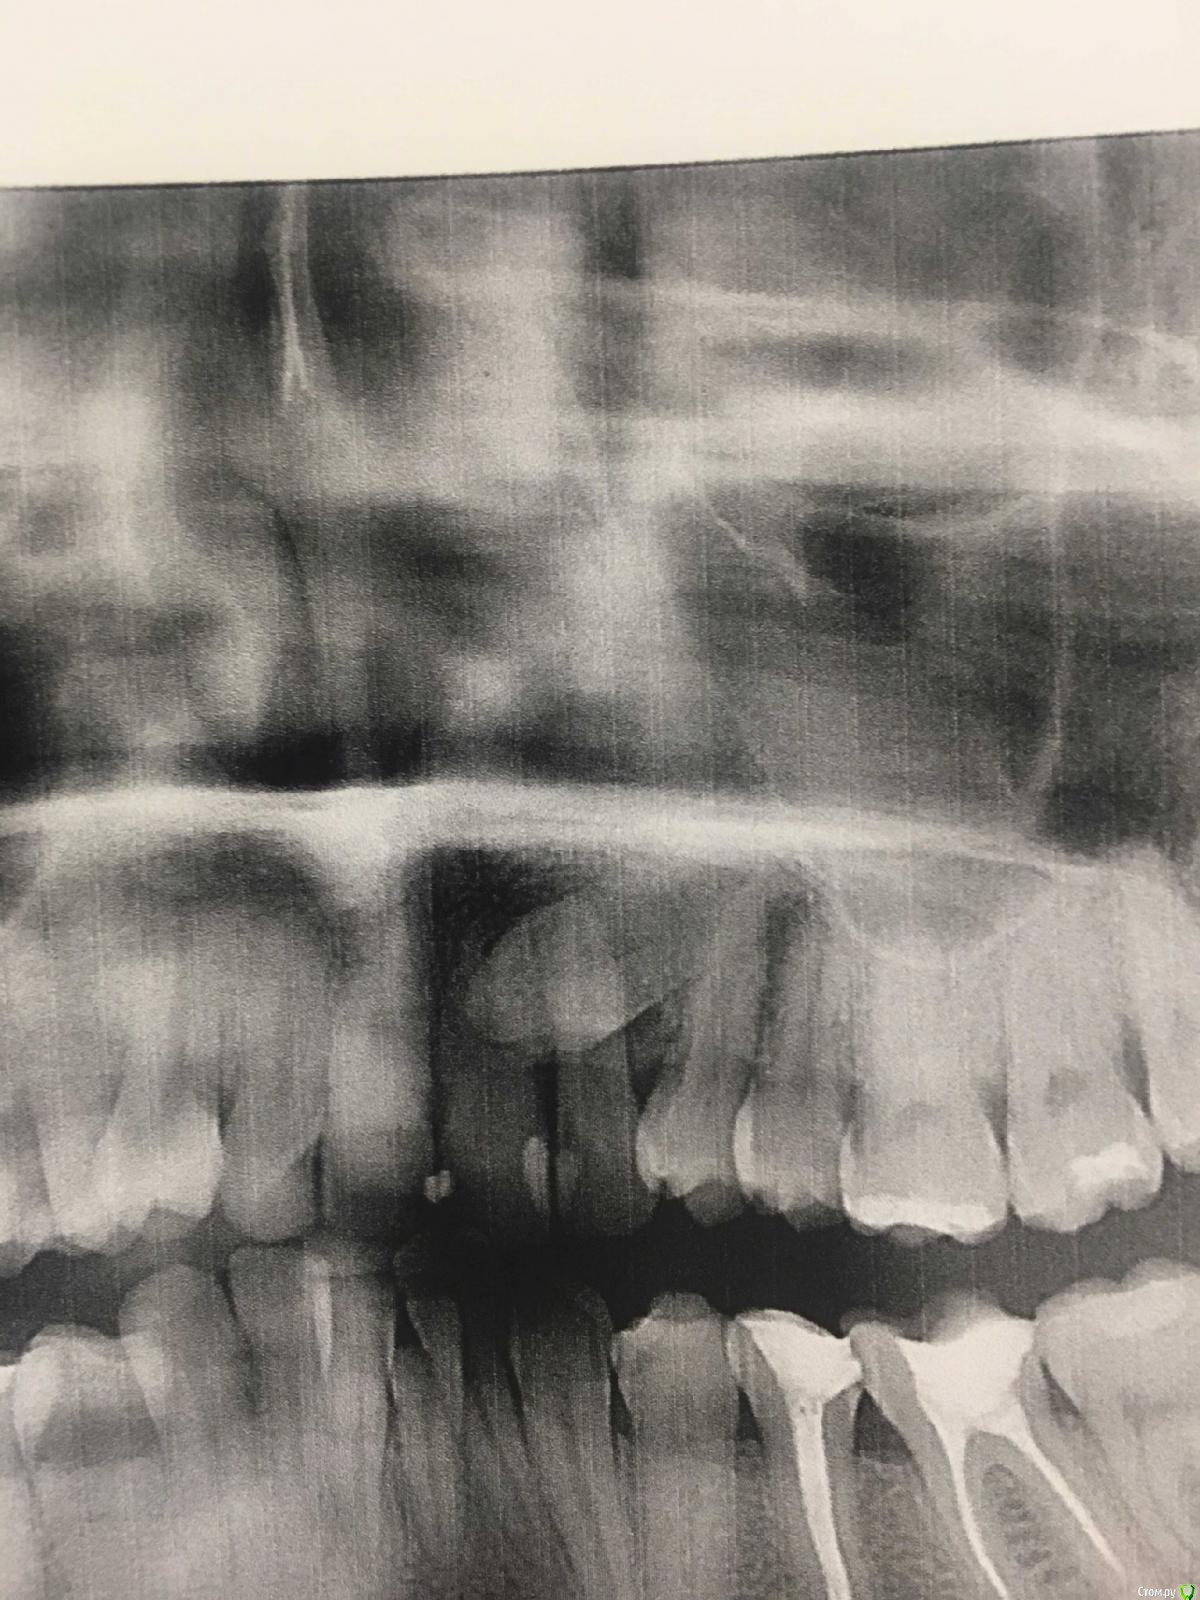

Уважаемые доктора, помогите пожалуйста! В моем городе только один врач-ортодонт, а выехать куда-либо на консультацию с другим специалистом, к сожалению, пока возможности не имею, а ситуация сложная. Суть вопроса такова. У меня есть ретинированный зуб, клык. В детстве я носила брекиты, лечение длилось три года. Тогда клык мне убирать не стали, просто выровняли зубной ряд, в результате на верхней челюсти сместился центр, а нижний ряд выпрямили. Ретейнеры не установили, в результате сейчас такая ситуация (фото). Спустя 15 лет решилась снова заняться решением своей проблемы, так как просто эстетикой это уже не ограничивается. Обратилась к тому же доктору, так как, повторюсь, доктор у нас один и работает с давних пор. Что она предлагает: 1) убрать ретинированный зуб 2) удаление одного зуба с нижней челюсти 3) установка брекит-системы и выравнивание. Прикус у меня глубокий. Дело в том, что при выравнивании зубного ряда сверху смещение центра ещё более усугубится ( я так предполагаю). И при удалении зуба с нижнего ряда тоже получится смещение. Хотелось бы узнать мнение, неужели нет альтернативных вариантов? Очень не хочется в результате получить смещённую челюсть((((. Вот так удалю зуб снизу по рекомендации доктора, а, как говорится, зуб не волос, новый не вырастет. Прошу, помогите пожалуйста(((.

Спасибо Вам огромное, что подсказали, небезразличным людям добро возвращается в стократном размере! А для меня это целая жизнь, с желанием жить ее без комплексов и в здравии)))Прикладываю фото!)